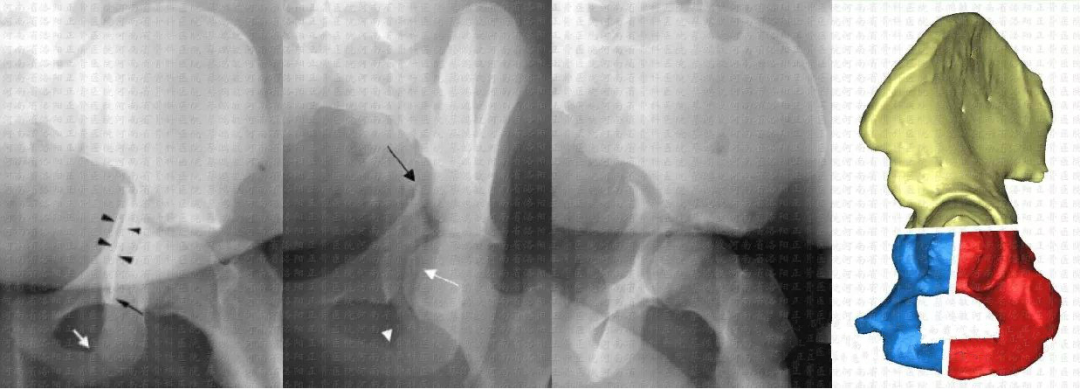

简单型     后壁骨折(25%)

简单型     后柱骨折(3%~5%)

简单型     横形骨折(5%~19%)

复杂型    后柱+后壁骨折(3%~4%)

复杂型    横形+后壁骨折(20%)

复杂型    T型骨折(7%)

复杂型    前柱/壁+后半横形骨折(7%)

复杂型    双柱骨折(23%)